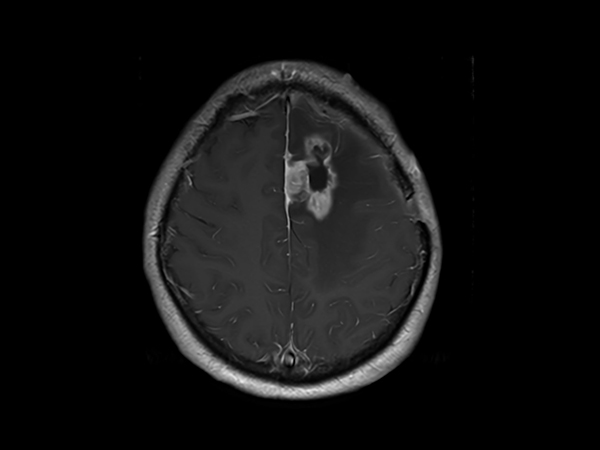

SmartSpeed Precise imaging for brain with glioblastoma

Kyushu University Hospital Japan